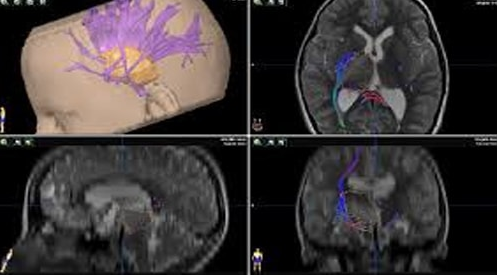

Neuro-navigation is the set of computer-assisted technologies used by neurosurgeons to guide or “navigate” within the confines of the skull or vertebral column during surgery. Neuro-navigation provides the ability to relate the position of a real surgical instrument in the surgeon’s hand or the microscope’s focal point to the location of the imaged pathology, updated in “real time” in an “integrated operating room”, highlights. In its current form, Neuronavigation began in the 1990s and has adapted to new neuro-imaging technologies, real-time imaging capabilities, new technologies to transfer the information in the operating room for 3-D localization has greatly improved surgical outcomes and reduced theatre times and maximized the ability to excise the pathology in most surgeriews. With neuro-navigation Neurosurgeon is able to visualize the scenario for surgery in a 3-D model of manipulable computer data. In this way the physician can “practice and check” the surgery, try alternative approaches, assess possible difficulties, etc., before the real surgery takes place.